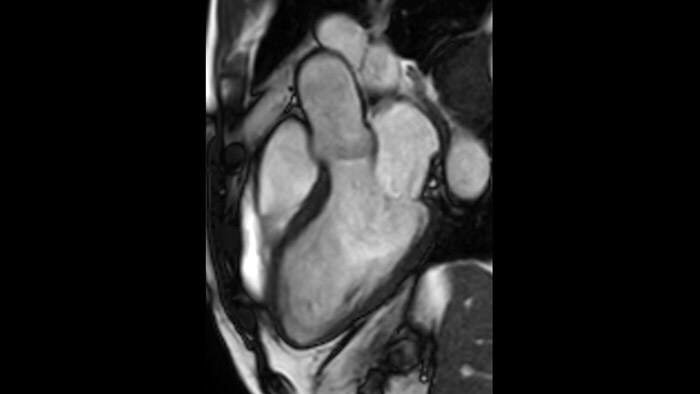

La utilidad diagnóstica y pronóstica de la RM cardíaca está aumentando. Evaluar la anatomía y función del corazón mediante adquisiciones cinematográficas, adquirir información sobre perfusión y viabilidad del tejido cardíaco, visualizar posibles edemas con secuencia de sangre negra, acceder e incluso cuantificar la caracterización tisular con CardiacQuant.